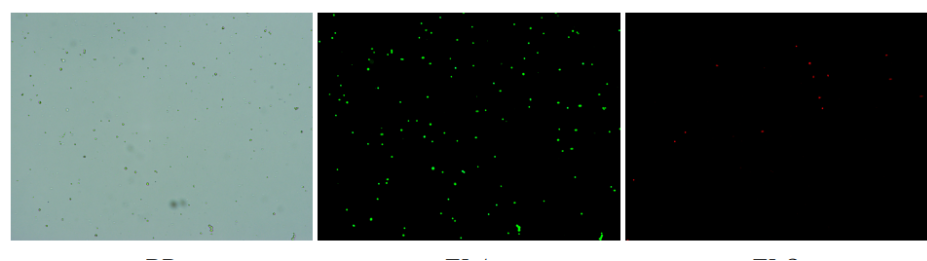

人肝癌樣本,懸液背景干凈,活性91.69%,結(jié)團(tuán)率6%